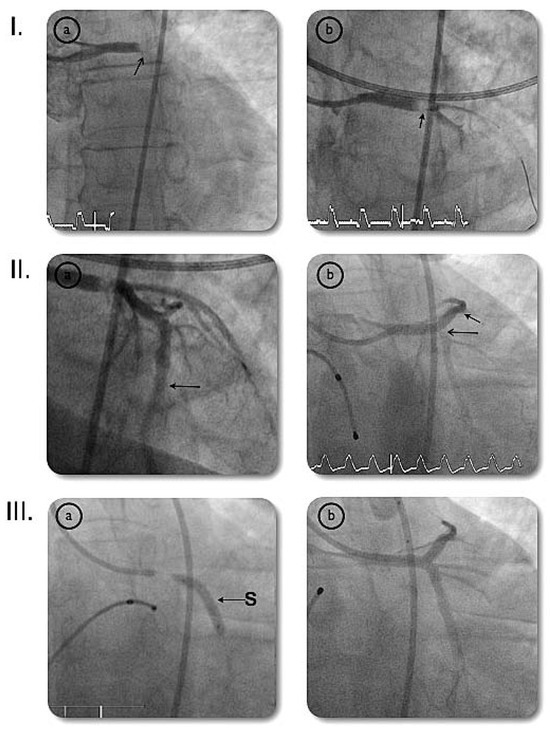

Asymptomatic Bland-White-Garland Syndrome in a 13-Year-Old Girl

by Jean-Pierre Pfammatter, Mladen Pavlovic and Stephan Windecker

An otherwise healthy 13-year-old girl was referred to the pediatric cardiology outpatient clinic for evaluation of a newly observed systolic murmur [...] Full article

Show Figures

Figure 1